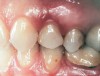

Second-stage surgery was performed after 4 months (Figure 8); healing abutments were placed and the soft tissue was allowed to heal for 5 more weeks. Then, splinted porcelain-fused-metal (PFM) crowns supported by custom gold abutments were delivered (Figure 9 and Figure 10).

Figure 9  Final implant-supported PFM restorations.

Figure 9